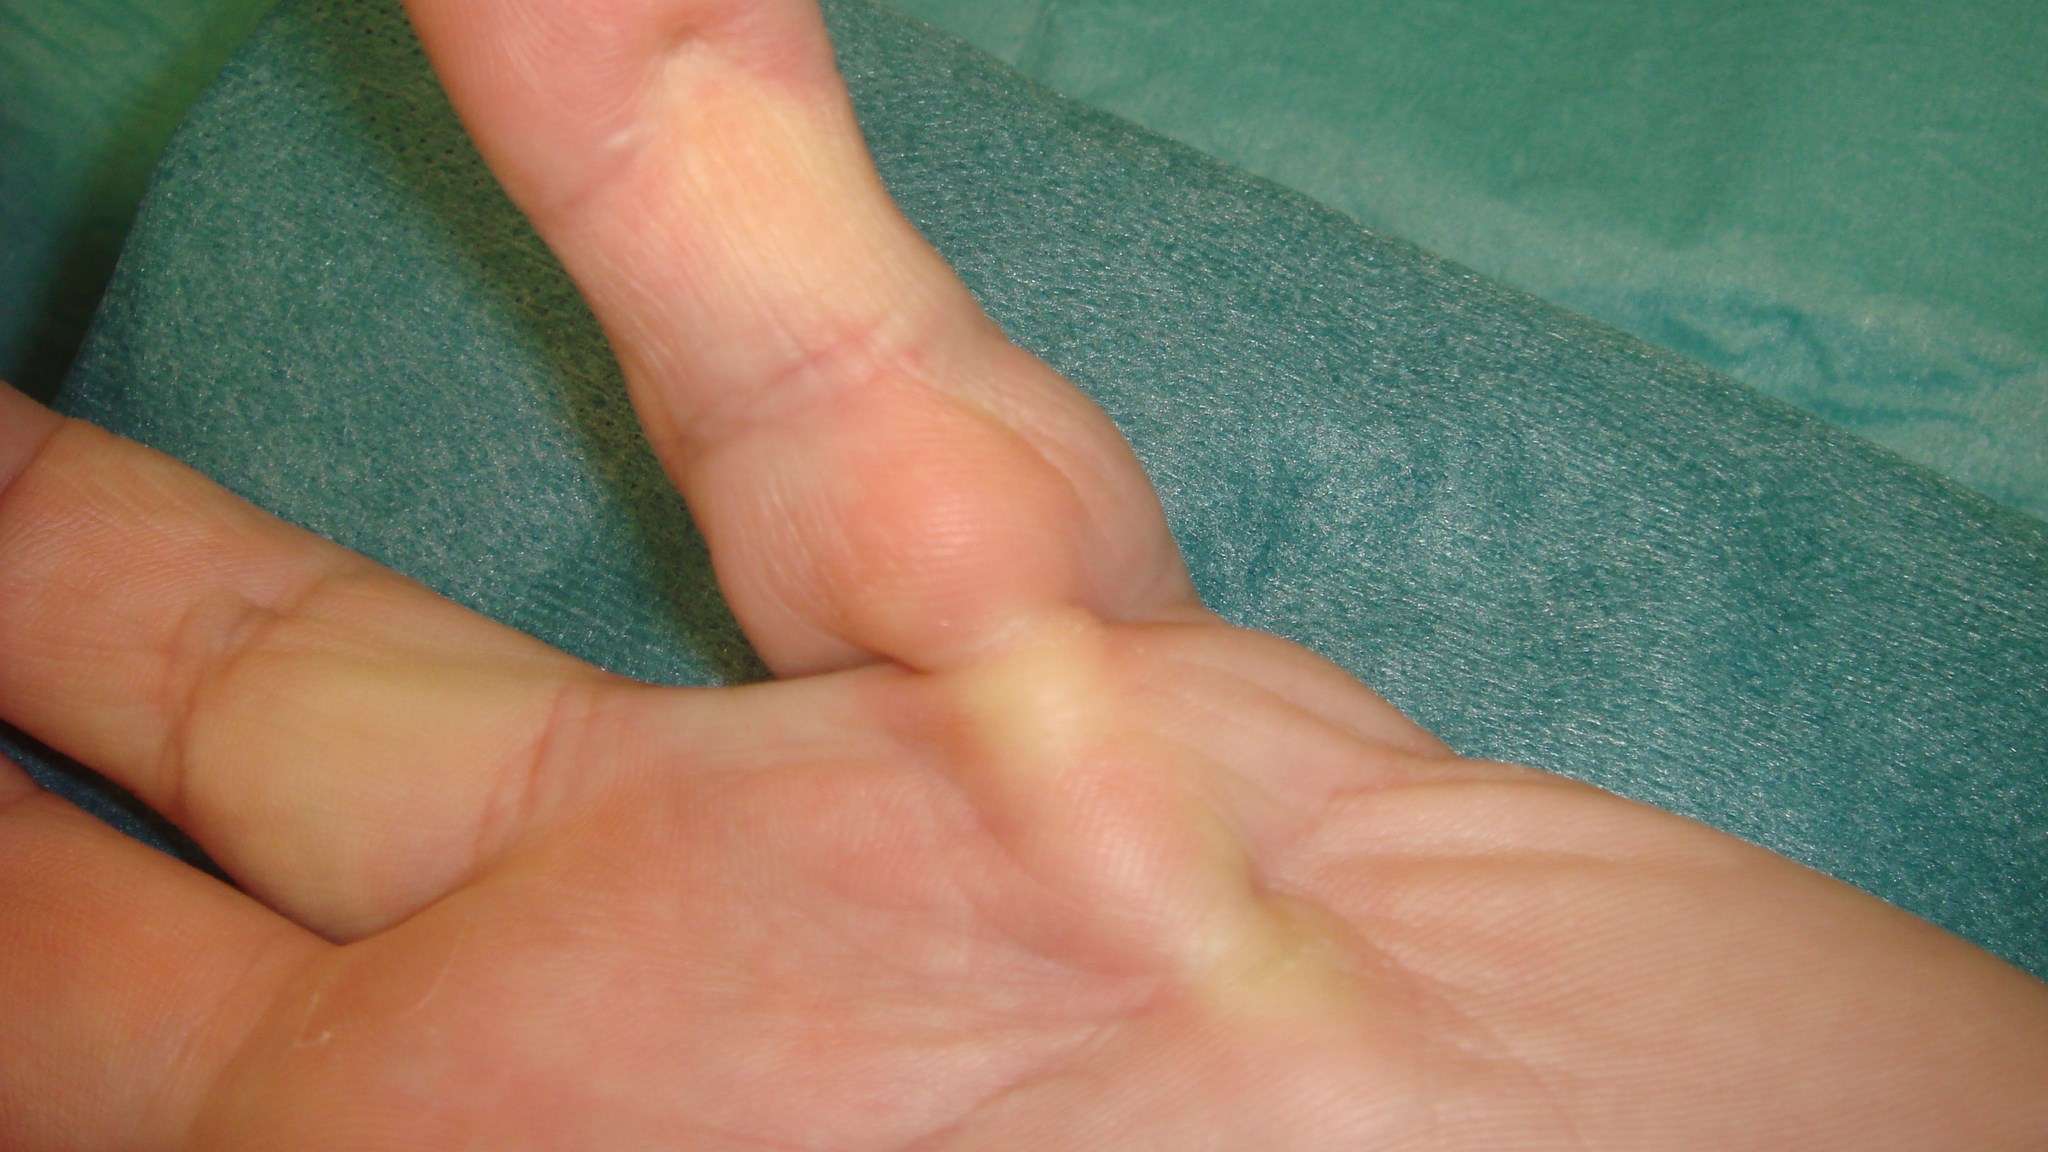

Volart i handflatan ser man tidigt nodulusbildningar (små förhårdnader), följt av riktiga strängar och ibland hudproblem med kryptabildningar (håligheter).

Strängarna formas efter att det bildats en noduli oftast i den ulnara delen av handen volart. Strängarna är inte smärtsamma och har ingen innervation men noduli kan vara smärtsamma när de uppkommer, tyvärr finns ingen behandling mot detta förutom smärtstillande.